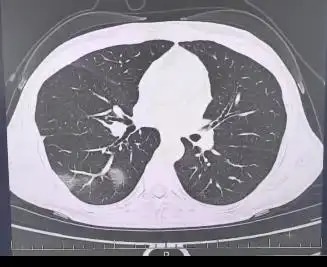

结果发现她好几叶肺都出现了“白肺”现象,指间血氧饱和度只有88%,血心肌酶谱、肌钙蛋白的指标、肝功能的指标也出现了明显的异常,最后证实得了重型流感。